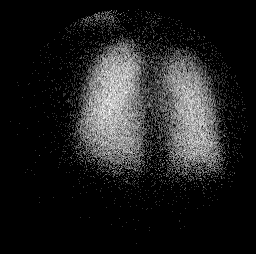

Posterior Perfusion Posterior Ventilation

perfusion1.gif (8591 bytes) vent1.gif (8676 bytes)